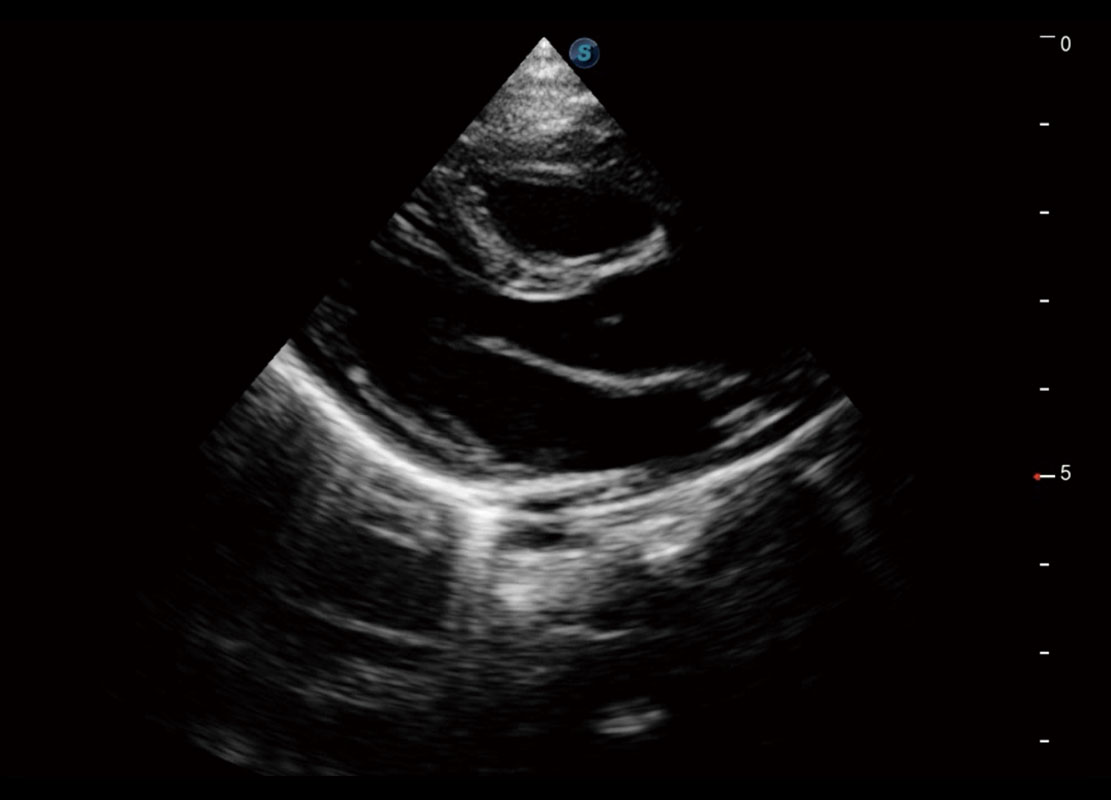

乳腺超声 / 新生儿

P60搭载宽频带线阵探头、宽景成像、弹性成像技术,为您提供乳腺应用方案。P60支持高频相控阵探头、线阵探头、腹部高频探头、腹部微凸探头等,丰富的探头群搭载敏感的彩色血流成像,适用于新生儿多种脏器检测要求,满足新生儿筛查需求。

• 新生儿心脏